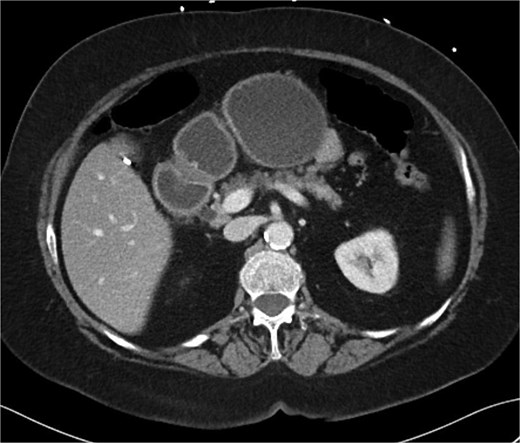

A 70-year-old woman with obesity, non-insulin-dependent diabetes, gastroesophageal reflux disease (GERD), cholecystectomy, and prior RYGB presented to the ED with acute chest and lower abdominal pain. The pain began 1 day earlier and initially responded to Ibuprofen, which she had been taking 4–6 times daily for musculoskeletal discomfort. Her pain worsened, radiating to her back, and was accompanied by belching and vomiting with dry heaving. She denied trauma or changes in bowel habits. Initial CT (Fig. 1) imaging showed a moderate hyperdense area around the duodenum, distension of the afferent limb and excluded stomach, and expected postoperative changes. She was admitted for conservative management. Four days later, a repeat CT (Fig. 2) was performed due to persistent symptoms, revealing free fluid in the intraperitoneal and retroperitoneal spaces, raising concern for duodenal perforation. She developed lethargy and diffuse abdominal tenderness and was taken to the operating room. Exploratory laparotomy with peritoneal washout, enterolysis, partial omentectomy was performed. It revealed two 1 cm posterolateral perforations of D3, which were repaired with an omental pedicle flap. The Roux limb was healthy, the jejunojejunostomy was dilated but patent, and the biliopancreatic limb was intact. Due to high vasopressor requirements, a temporary abdominal closure device was placed, and she was transferred to the surgical ICU. After stabilization, a second-look laparotomy was performed the next day to reinforce the duodenal closure, place a gastrostomy tube for drainage, and insert a J-tube for feeding (Figs 3 and 4). The abdominal wall was closed. On postoperative day 2, a CT with contrast showed extravasation from the duodenal repair site. Interventional radiology placed a transhepatic biliary drain to divert bile and support duodenal patch healing. Helicobacter pylori antigen was negative. Her condition improved, and she was started on an enteral and slow oral feeding regimen. However, at this juncture, the patient declined further treatment and requested comfort care measures.

Intra-operative image showing primary repair of D3 duodenal perforation.